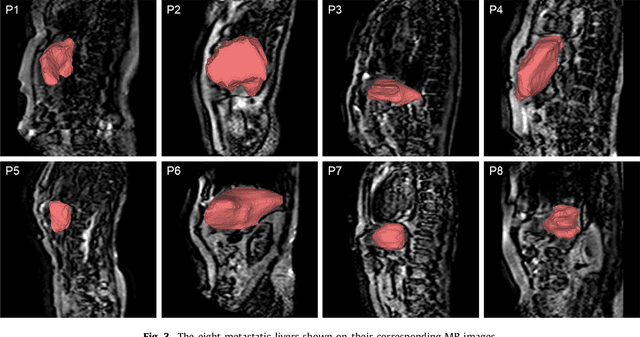

Abstract:Real-time 3D navigation during minimally invasive procedures is an essential yet challenging task, especially when considerable tissue motion is involved. To balance image acquisition speed and resolution, only 2D images or low-resolution 3D volumes can be used clinically. In this paper, a real-time and registration-free framework for dynamic shape instantiation, generalizable to multiple anatomical applications, is proposed to instantiate high-resolution 3D shapes of an organ from a single 2D image intra-operatively. Firstly, an approximate optimal scan plane was determined by analyzing the pre-operative 3D statistical shape model (SSM) of the anatomy with sparse principal component analysis (SPCA) and considering practical constraints . Secondly, kernel partial least squares regression (KPLSR) was used to learn the relationship between the pre-operative 3D SSM and a synchronized 2D SSM constructed from 2D images obtained at the approximate optimal scan plane. Finally, the derived relationship was applied to the new intra-operative 2D image obtained at the same scan plane to predict the high-resolution 3D shape intra-operatively. A major feature of the proposed framework is that no extra registration between the pre-operative 3D SSM and the synchronized 2D SSM is required. Detailed validation was performed on studies including the liver and right ventricle (RV) of the heart. The derived results (mean accuracy of 2.19mm on patients and computation speed of 1ms) demonstrate its potential clinical value for real-time, high-resolution, dynamic and 3D interventional guidance.